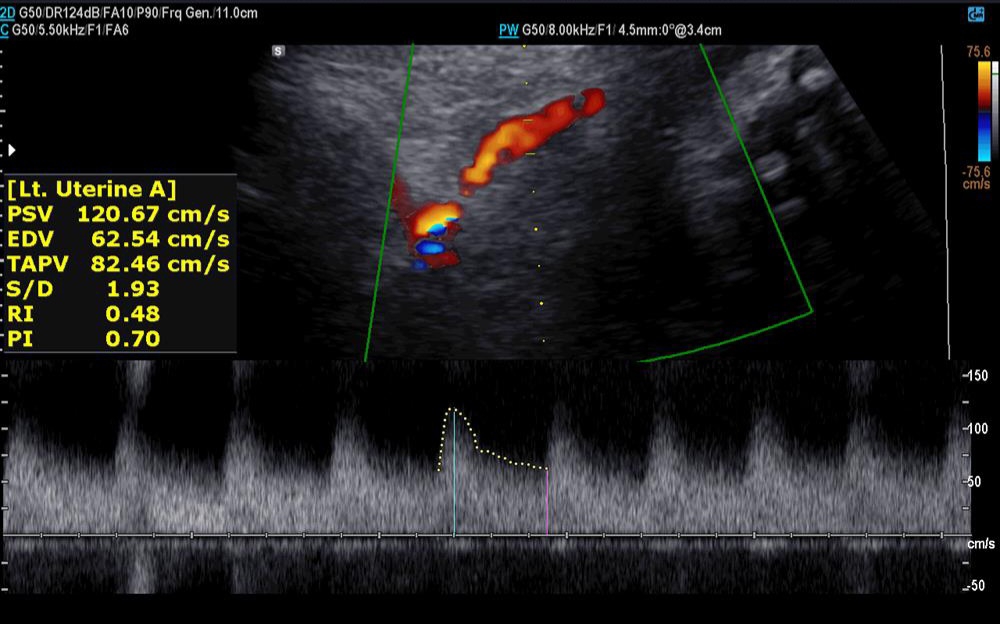

✅️✅️✅️تفسیر سونو داپلر۳۶ هفته🙏🏻

خداروشکر شواهد رشدی بهتر شده و در سونوگرافی شواهدی به نفع محدودیت رشد داخل رحمی و همچنین کمبود اکسیژن جنین وجود ندارد ولی مقداری مقاومت شریانی دارید به پزشکتان حتما مراجعه کنید تا درمورد زایمان و یا شروع انوکساپارین تصمیم گیری شود

جانم pi 2.4 ولی تحت نظر باشید مشکلی ندارد